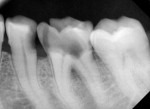

Clinical examination revealed the presence of gingival tissue through the access opening at the mandibular left first molar that occurred at a private clinic (Figure 1). Upon radiographic examination, the mandibular left first molar showed a perforation on the distolingual aspect of the pulpal floor. Proximal caries was also present in the adjacent premolar (Figure 2).